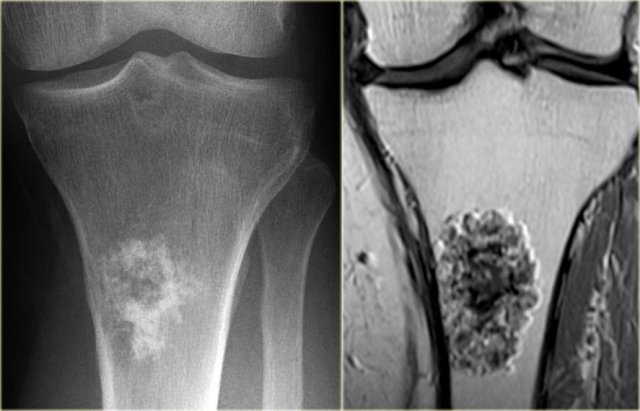

Chondroblastoma (8)

Here lesion in the proximal tibia in a 20 year old.

Key findings:

• Epiphyseal lesion

• Lobulated margins

• Extensive edema

• Young patient.

Diagnosis: Chondroblastoma.

Diff. diagnosis: Osteomyelitis.